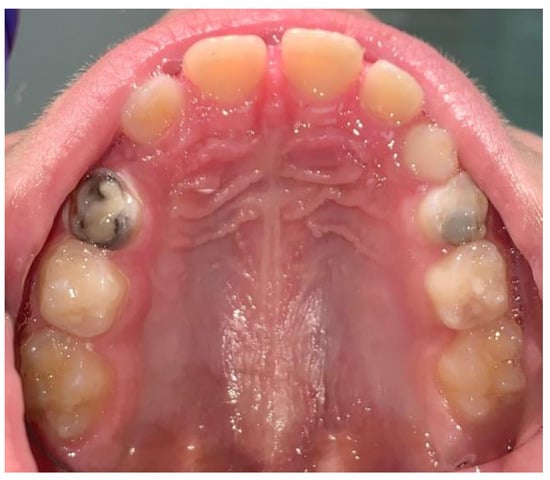

- Wambier, D.S.; Chibinski, A.C.R.; Wambier, L.M.; de Lima Navarro, M.F.; Banerjee, A. Minimum Intervention Oral Care Management of Early Childhood Caries: A 17-Year Follow-up Case Report. Eur. J. Paediatr. Dent. 2023, 24, 20–29. [Google Scholar] [CrossRef]